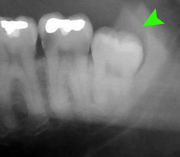

If the tooth cannot be assessed with clinical exam alone, the diagnosis is made using either a panoramic radiograph or cone-beam CT. Where unerupted wisdom teeth still have eruption potential several predictors are used to determine the chance of the teeth becoming impacted. The ratio of space between the tooth crown length and the amount of space available, the angle of the teeth compared to the other teeth are the two most commonly used predictors, with the space ratio being the most accurate. Despite the capacity for movement into early adulthood, the likelihood that the tooth will become impacted can be predicted when the ratio of space available to the length of the crown of the tooth is under 1.[3]:141